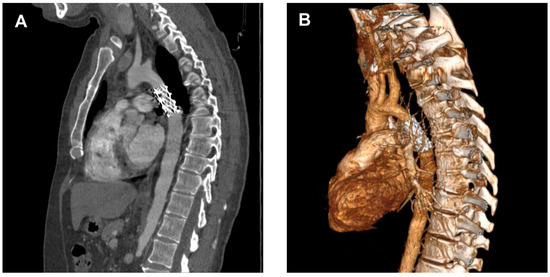

Endovascular Repair of Thoracic Aortic Atresia in Adults: A Narrative Review of a Rare Entity and Emerging Technique

Thoracic aortic atresia in adults represents a rare and extreme manifestation of aortic coarctation, marked by complete luminal occlusion and frequently compensated by extensive collateral circulation. This narrative review critically evaluates existing literature and institutional experience concerning surgical and endovascular repair strategies for [...] Read more.

Thoracic aortic atresia in adults represents a rare and extreme manifestation of aortic coarctation, marked by complete luminal occlusion and frequently compensated by extensive collateral circulation. This narrative review critically evaluates existing literature and institutional experience concerning surgical and endovascular repair strategies for aortic atresia, synthesizing evidence from related aortic arch pathologies due to the absence of direct comparative studies. Both treatment modalities—open surgical repair and catheter-based recanalization with stenting—have evolved significantly, presenting distinct advantages and limitations influenced by patient anatomy, age, and comorbidities. While surgical repair remains the standard for neonates, infants, and complex cases due to superior long-term durability and blood pressure control, endovascular procedures using chronic total occlusion technique and covered stents offer less invasive alternatives with rapid recovery, particularly in adults with suitable anatomic characteristics. The review highlights procedural considerations, including technical approaches, stent selection, and potential complications such as restenosis, hypertension, and vascular injury. Individualized, multidisciplinary decision-making remains essential, with shared consensus guiding therapy in the absence of randomized trials. The article identifies critical gaps in knowledge, emphasizing the need for multicenter, long-term studies and technological advances—including hybrid and personalized strategies for optimal management and for improving outcomes in this challenging congenital condition. Full article

Show Figures

Figure 1